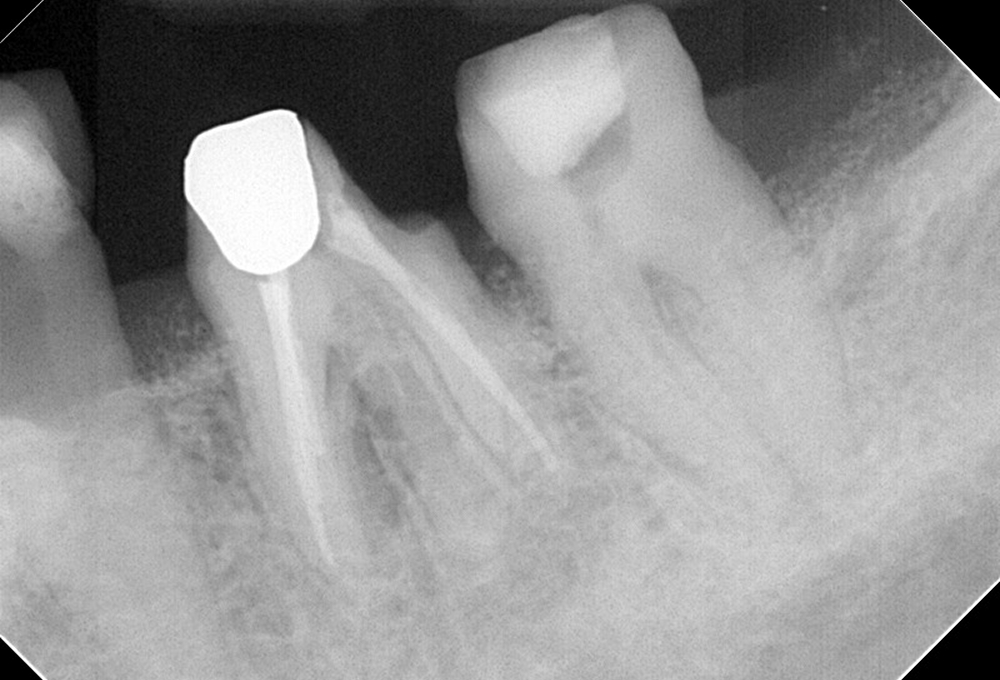

①術前 下顎小臼歯の根尖病変 未処置根管有

②根管充填後 未処置根管も治療 根尖病変も縮小した